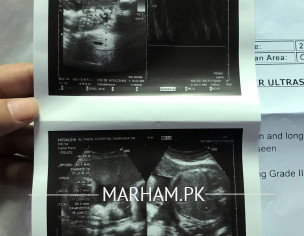

Asslam o alikum doctors mujhy pouchna tha Maine 4 May ko colour Doppler ultrasound karwaya tha us main mery 34 weeks complete thy jo k counting k hisab sy Thek thy Ak 15 May ko doctor ko check karwaya hai to wo keh Rahi hain ap k 32 weeks hain abi ye Kyn itna difference aa raha jb k inko Maine 2 weeks pehly bhi check karwaya tha tab bhi mery 32 weeks thy or Aj bhi wo keh Rahi thi scanning main itna difference aa jata hai Kya ye normal hai ???Report attach ki hain plz check Kar k btaye ga

wa alaikum salam yes it is normal in last months of pregnancy but its better to repeat scan from doctor who did the scan of 34wks

2 week difference is normal .Doppler also normal u can repeat after 2 weeks with same doctor